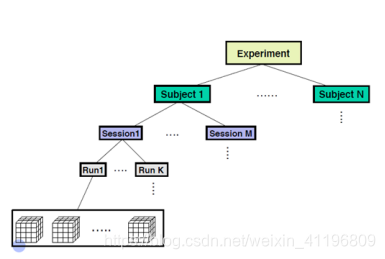

在一个实验中,通常我们都会选取很多被试(subject)去做相同的任务(task)。每一个被试会参加很多轮扫描(sessions),在一轮里又会被扫描很多次(run)。我们通常会让被试重复完成几次实验任务。每一次扫描都会得到很多数据。每一次有很多体素,每个体素都有一个自己的强度值。这也是最基础的测量值。所以整个实验的数据就是这样一层层下来的,一个实验有很多被试,每个被试会参加很多轮扫描。每次扫描又会扫描很多次。每次扫描又会包含很多体素。